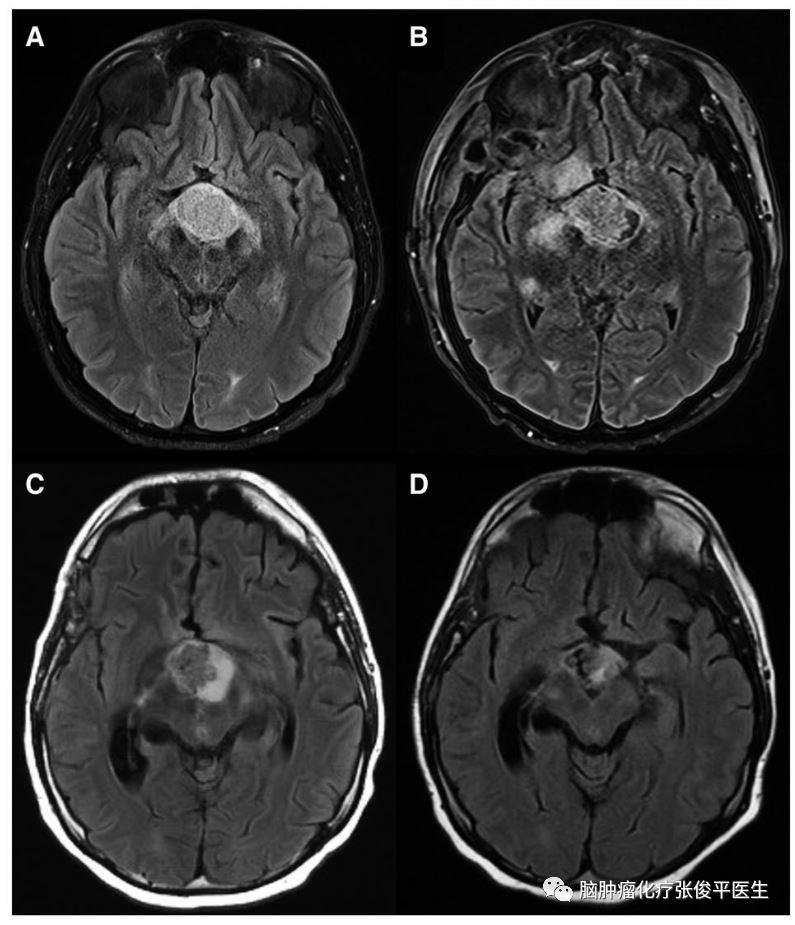

图:病例6的MRI检查结果:T2-FLAIR像可见鞍上囊实性占位。

A:确诊时;B:术后;C:达拉非尼联合曲美替尼治疗2周后;D:治疗6月后。

病例6为21岁男性患者,主因间断头痛和疲劳起病。眼科检查示视野缺损。MRI检查示鞍上异常强化病灶。该患者接受手术治疗,部分切除肿瘤,术后病理证实为PCP,存在BRAFV600E突变。手术并发脉络膜前动脉供血区域的梗死和垂体功能严重减退。术后1月患者复查MRI示肿瘤进展,并开始靶向治疗。6月后肿瘤显著缩小,头痛和精神状况明显改善。